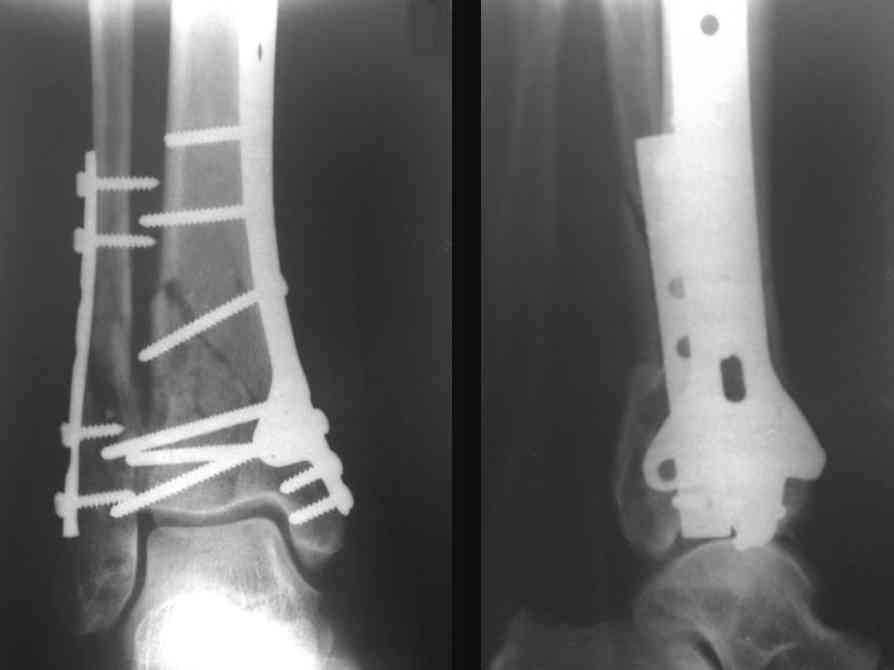

Послала ещё два снимка, если не пройдут, пошлю ещё. Дрягин. Если есть вопросы, готов ответить.

Посылаю результат лечения предыдущего больного через год.

С уважением Дрягин

Кстати, при переломах переднего края по классификации АО В-3 при переломах пилона пластина укладывается по передней поверхности. Она достаточно тонкая и эластичная, не надо этого бояться. Посылаю три снимка.